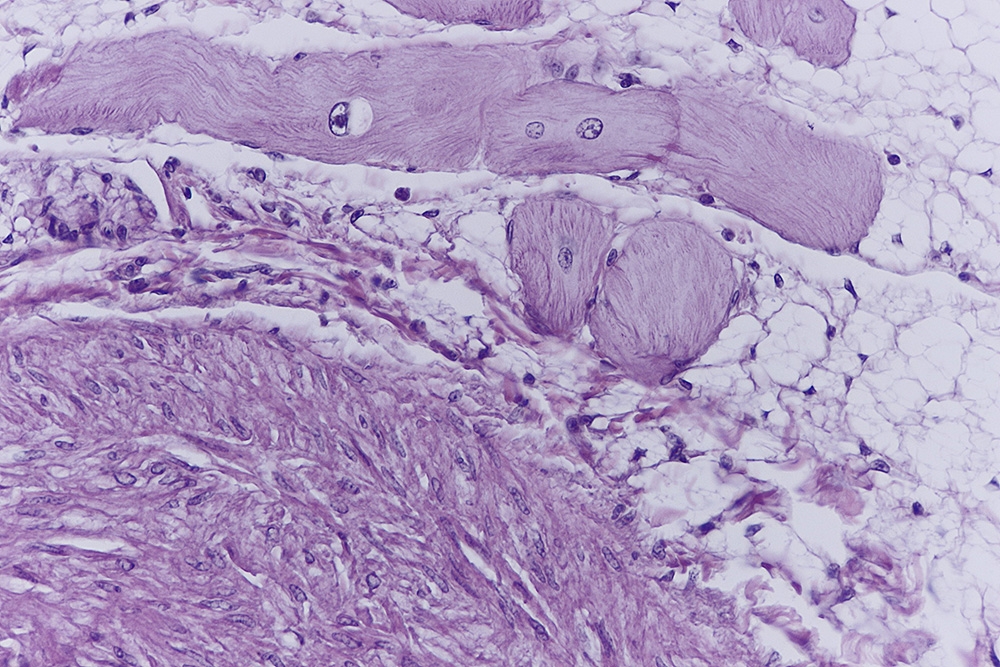

Die Purkinje-Fasern als spezialisierte Herzmuskelzellen, bilden den letzten Teil der

Impulsleitung mit direktem Übergang in die Myocardzellen.

Diese, oft als ,,Möpse" beschriebenen Zellen, liegen im Inneren der Herzkammern

zwischen Endocard und Myocard in einer Schicht aus lockerem Bindegewebe zusammen

kleinen Blutgefäßen und nicht myelinisierten Nerven.

Was mich aber auch interessierte war wie das in Kunststoffschnitten aussieht, und wie der Strukturerhalt ist. Also habe ich in Technovit 7100 umgebettet und bei 1,5µ geschnitten.

Was mir aber sehr gefällt, ist der schöne Strukturerhalt nach dem Umbetten.

Vielleicht ist auch das Reizleitungssystem beim Vogel ausgeprägter, denn so habe ich es beim Menschen und bei Nagern nie gefunden. Viele interessante Fragen.